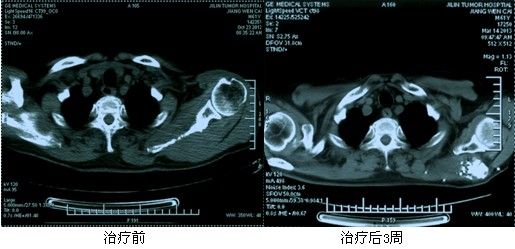

典型病例:姜XX,男,61歲,原發(fā)性肝右葉癌(BCLC C期)、多發(fā)性骨轉(zhuǎn)移癌。左側(cè)肩胛骨發(fā)生轉(zhuǎn)移,左肩背部疼痛明顯。給予125I放射性粒子植入后疼痛癥狀明顯減輕,病灶明顯萎縮。